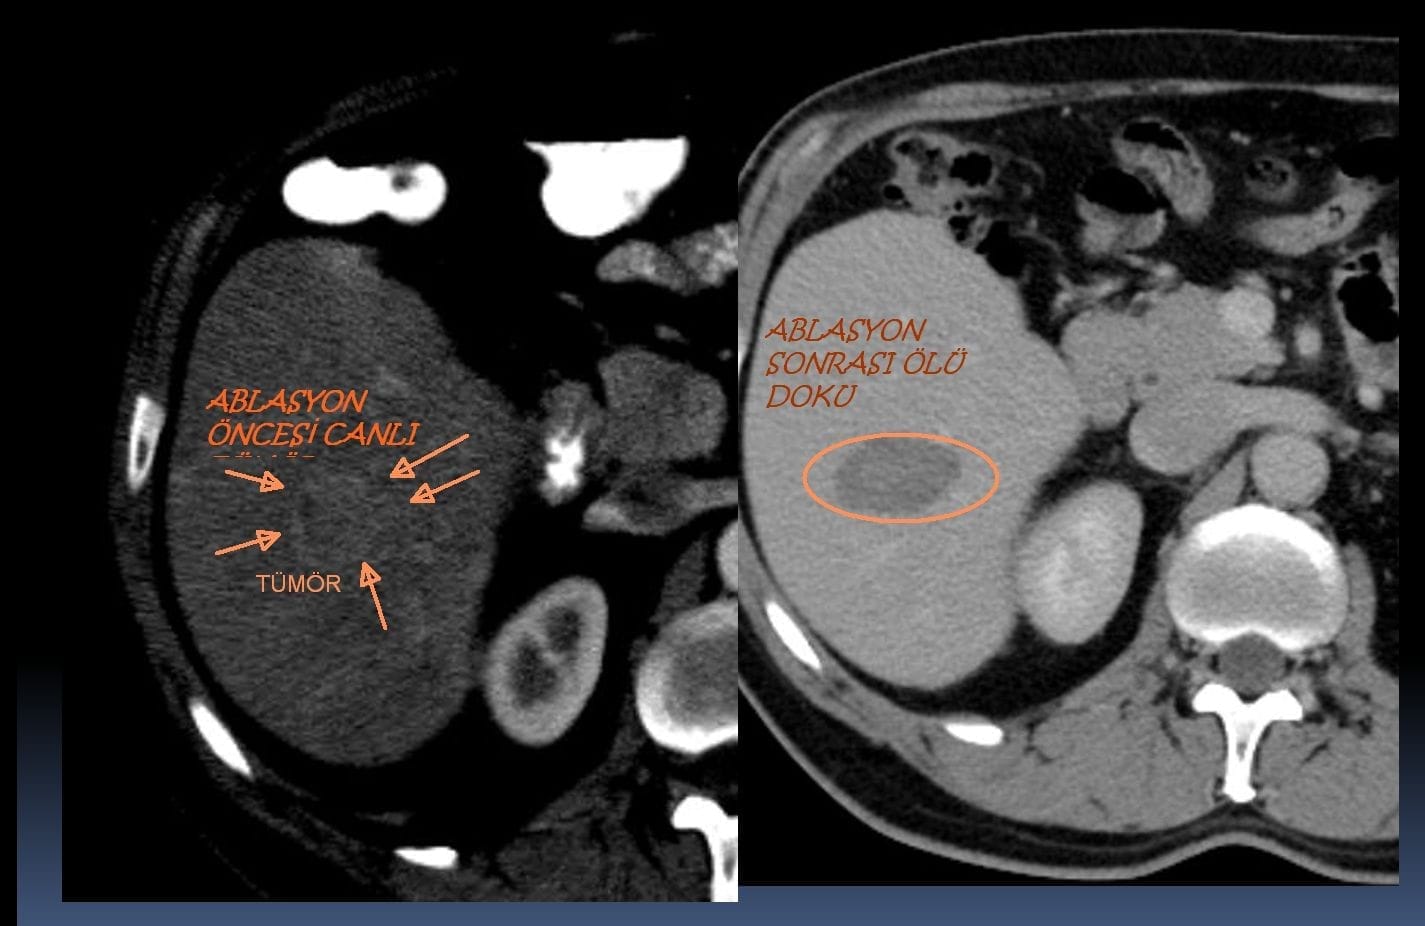

Karaciğer tümör ablasyon tedavisi sonrası düzenli görüntüleme ile tedavi etkinliği ve tümör kontrolü değerlendirilir. Nüks halinde ek seans planlanabilir.

Karaciğer tümörleri için ablasyon tedavisi, kanserli dokuyu yok etmek amacıyla radyofrekans ablasyonu (RFA) ve mikrodalga ablasyonu (MWA) gibi minimal invaziv tekniklerle uygulanır. RFA, yüksek frekanslı elektrik akımlarıyla ısı üretirken, MWA elektromanyetik mikrodalgaları kullanır. Bu işlemler genellikle ultrason veya BT gibi görüntüleme kılavuzluğunda, perkütan, laparoskopik veya açık cerrahi sırasında gerçekleştirilir. Ablasyon, cerrahi rezeksiyon için uygun olmayan erken evre hepatoselüler karsinom (HCC) veya metastatik karaciğer tümörleri olan hastalar için tercih edilir. RFA ve MWA seçimi, tümörün boyutu (≥3 cm olanlarda genellikle MWA tercih edilir), konumu ve kan damarlarına yakınlığı gibi faktörlere bağlıdır. MWA, daha yüksek intratümoral sıcaklıklar ve daha hızlı ablasyon süreleri sağlayarak büyük tümörler veya büyük damarlara yakın tümörler için avantajlıdır. Her iki yöntem de lokal nüks riskini en aza indirmek için lezyon etrafında en az 10 mm’lik bir güvenlik marjıyla tam tümör nekrozu sağlamayı hedefler. İşlemler genellikle iyi tolere edilir, düşük komplikasyon oranına sahiptir ve gerektiğinde tekrarlanabilir. Bununla birlikte, ablasyon tedavisinin etkinliği, tümör özellikleri ve tıbbi ekibin deneyimine bağlıdır.

Evet, karaciğer tümörleri ablatif tedavi sonrasında tekrar edebilir. Mikrodalga ablasyon (MWA) sonrası 1 yıllık hastalıksız sağkalım oranı yaklaşık %80,2 olup, bu oran 3 yılda %70,3’e düşmektedir. Tümör büyüklüğü, yetersiz ablasyon marjları, birden fazla lezyon ve Child–Pugh B gibi karaciğer fonksiyon sınıflamaları nüks riskini artıran faktörler arasındadır. Ayrıca tümörün konumu ve yüksek alfa-fetoprotein seviyeleri nüks oranlarını etkileyebilir. Nüksleri erken tespit ve tedavi edebilmek için düzenli takip önemlidir.